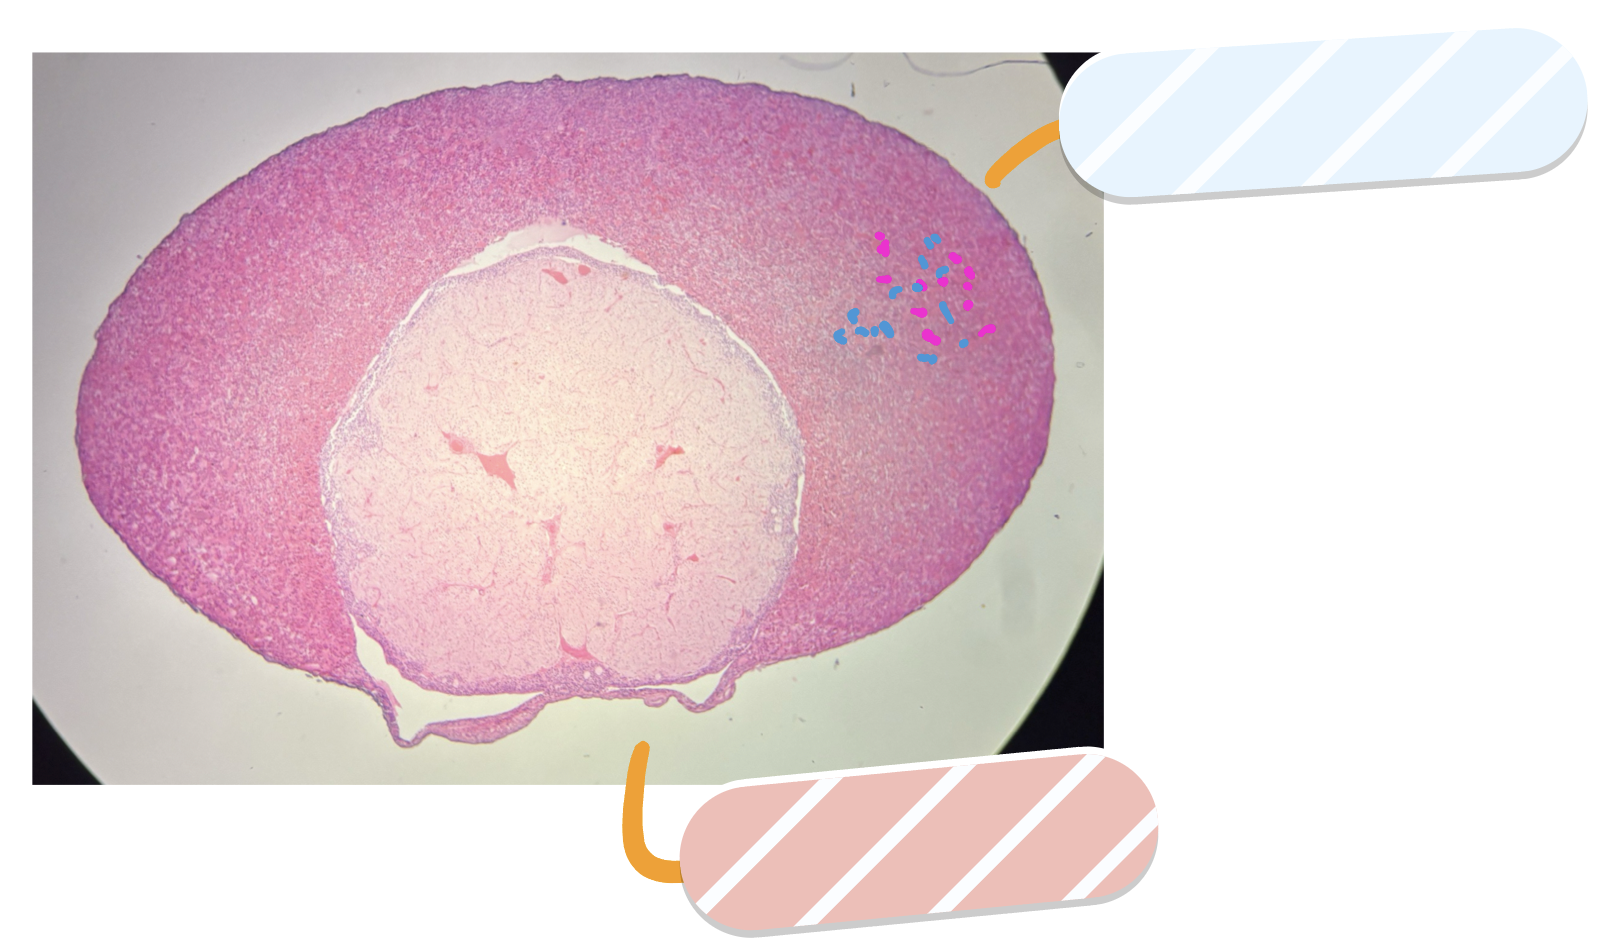

What is this a slide of?

Pituitary gland

What label is covered by white?

Anterior pituitary

What label is covered by salmon?

Posterior pituitary

What three cells are found in the section labeled by white?

Acidophils, basophils, “chromophobe” cells

The hormones stored in the salmon section are secreted by what?

Hypothalamus

The pink cells in the white-labeled section release what hormone?

Growth hormone and prolactin

The blue cells in the white labeled section secrete what hormones

Follicle-stimulating hormone, Luteinizing hormone, Adrenocorticotropic hormone, Thyroid stimulating hormone

What two structures should you note in the salmon-labeled section?

axon endings and neuroglial cell nuclei

The axons in the salmon-labeled section are from what?

hypothalamic neurons in paraventricular and supraoptic nuclei

Salmon-labeled section secretes what hormones

Oxytocin and antidiuretic hormone